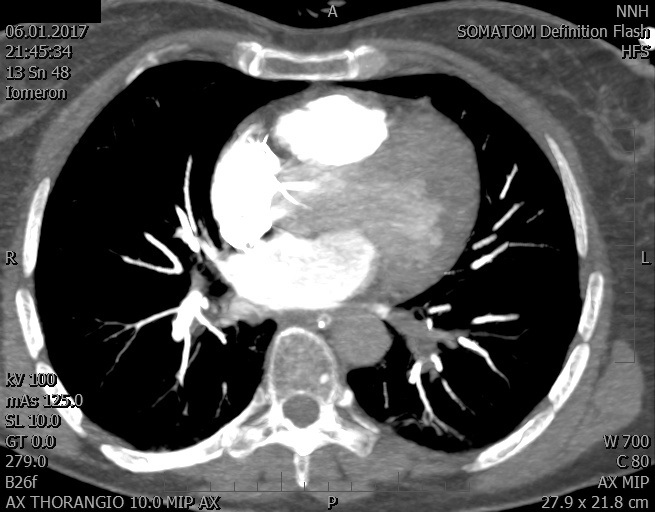

Video 2 - Echokardiograficky byla zjištěna těžká dysfunkce dilatační levé komory s nezvětšenou pravou komorou.Pro nejasnou příčinu zástavy jsme provedli i vyšetření výpočetní tomografií (CT), které vyloučilo plicní embolizaci (série 1 - soubory na konci článku). V den přijetí při přetrvávající oběhové nestabilitě byla nemocná opakovaně defibrilována pro fibrilaci komor se stabilizací rytmu po podání amiodaronu a mesocainu. Dle hemodynamických měření se jednalo o těžký kombinovaný šok. Vstupní laboratorní vyšetření bylo bez větších pozoruhodností. Posléze jsme doplnili anamnézu od příbuzných a zjistili, že pacientka užila do dvou hodin před srdeční zástavou první tabletu amoxicilinu na lehký respirační infekt. Při nevýtěžnosti vstupních vyšetření a nových anamnestických informacích jsme doplnili 14 hodin po kolapsu vyšetření koncentrace tryptázy v séru, která byla extrémně zvýšena (tabulka 2), což nás vedlo k podezření na anafylaxi.